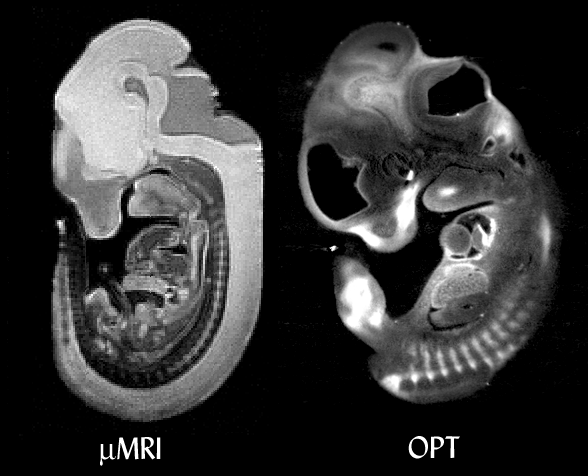

Comparison between mMRI and OPT. In both cases the specimen is an E11.5 mouse embryo. The mMRI image shows higher contrast between tissues, while OPT shows greater resolution. The OPT-scanned embryo was also stained for the expression of Sox9 with a coloured dye (BCIP/NBT), which can be seen as the white regions. mMRI cannot image common assays like this. MRI data courtesy of R. Jacobs and S. Ruffins (see the Caltech MRI mouse atlas project).

Close-up of the two reconstructions. A similar plane of section is shown from each embryo, at approximately the same magnification. Both embryos are facing left, with the front of the face at top left with nasal cavities visible in each, the branchial arch top centre, and tissues of the heart seen in the middle of each image. Thin membranes are not visible in the mMRI data. MRI data courtesy of R. Jacobs and S. Ruffins (see the Caltech MRI mouse atlas project).